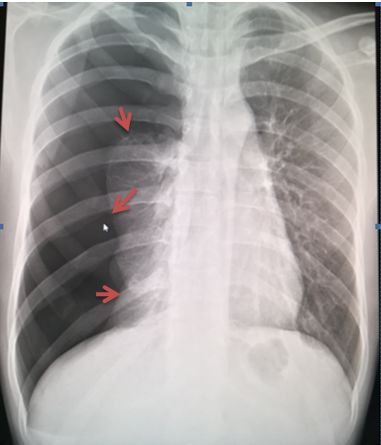

病例5患者左肺野外带可见无血管纹理区及肺叶压缩带边缘(红色箭头),肺叶压缩约5%

点拨:有时肺组织压缩边缘全部或部分与肋骨走行重合,可以通过调节负相帮助进一步观察。